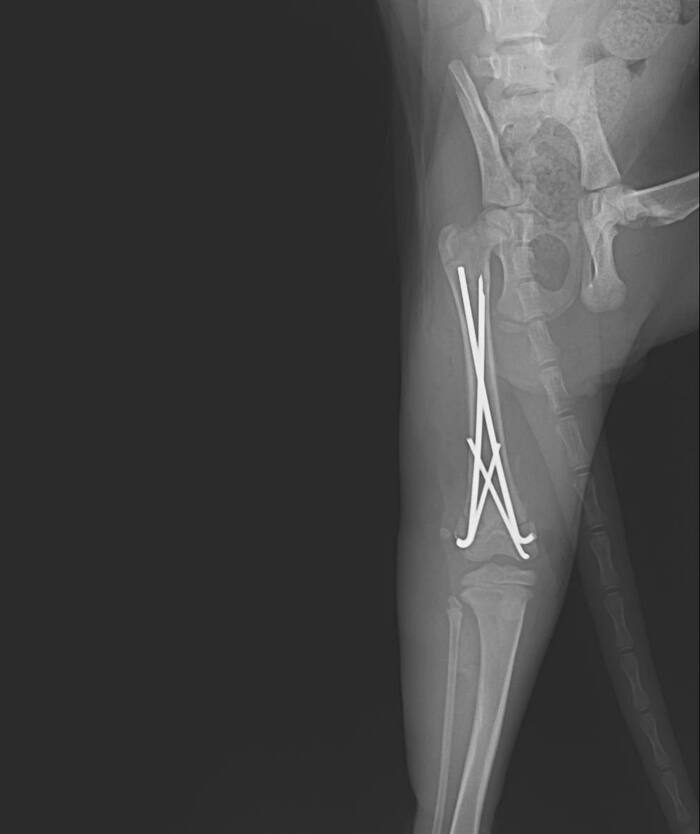

Далее у коти была операция с установкой спиц и последующем их извлечением, деньги на операцию собрали сотрудники ТЦ за пару часов.

Вот здесь Ириска за несколько дней до удаления спиц, увидела и пощупала лес (двигаться ей можно было, а прыгать и падать с высоты нельзя, по этому дома она почти месяц жила в клетке для кошек):